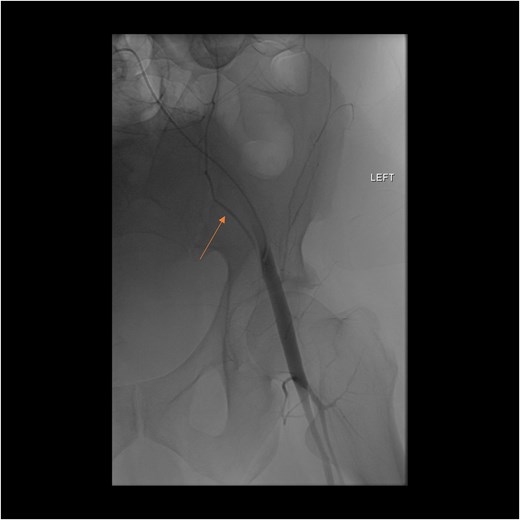

A follow-up CT scan performed 2 days after placement of IVC filter and stopping anticoagulation showed further enlargement of the hematoma (17.5 × 14 × 25.7 cm) and ongoing bleeding. Interventional radiology performed bilateral inferior epigastric artery angiograms, which revealed no ongoing artery bleeding but truncation of the right inferior epigastric artery. Empiric Gelfoam embolization was performed on the left inferior epigastric artery (Fig. 4).

Angiogram of the left inferior epigastric artery (arrow) demonstrating no active bleeding.